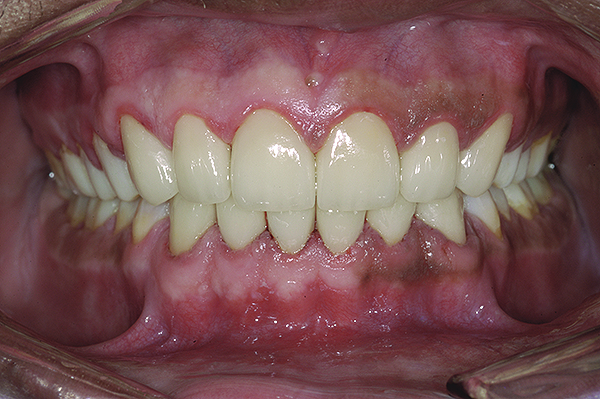

Figure 19. Postoperative frontal smile.

Figure 19

Figure 20. Postoperative 1:2 retracted frontal view.

Figure 20

The final restorations depicted restoration of form, function, and beauty, with good harmony of restoration and the periodontium (Figure 19 through Figure 25). MIP was in harmony with CR, and right and left lateral excursion discluded all posteriors with anterior group function. The postoperative orthopantomogram (OPG) (Figure 26) shows the treatment done while maintaining the vitality of anterior teeth.